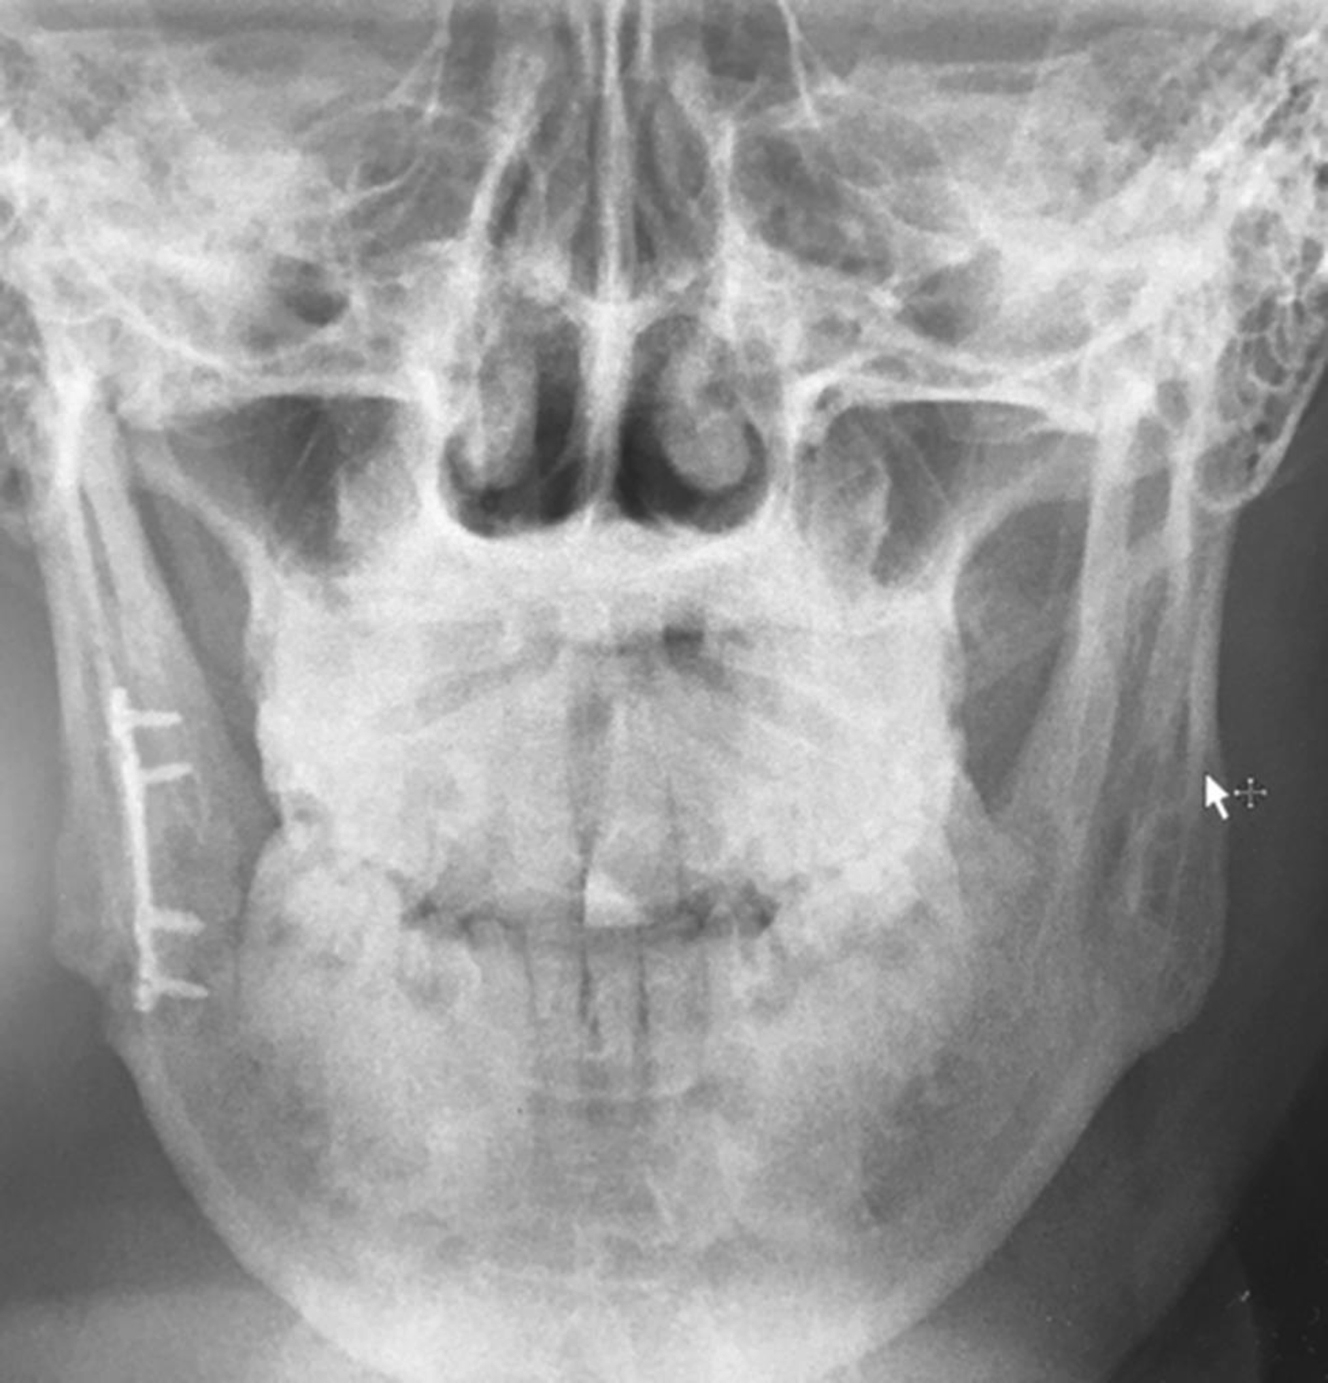

The lateral inferior boarder also can be used for load-bearing rigid fixation using bicortical screws and thick plates designed to bear the complete load of mandibular function. Three holes on each side of the fracture would be considered the minimum optimal engineering necessary to accomplish safe immediate function. The placement of such thick and large hardware in this position is often accomplished through an external skin incision to allow optimal exposure for plate placement and plate contouring. The choice of this technique is made when fractures are comminuted, when the mandible is edentulous and atrophic with loss of alveolar bone stock, or when there is tooth loss which reduces contact surface area. Load-bearing approaches are also preferential in circumstances where infection is present ( Fig. 7 ).